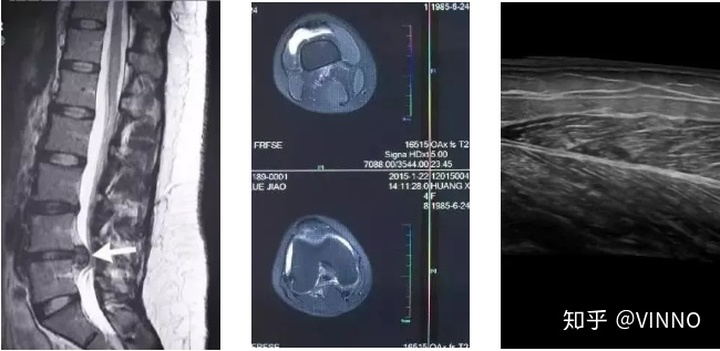

▲ 这是核磁共振对比影像

▲ 这是CT断层扫描影像

▲ 这是超声扫描影像